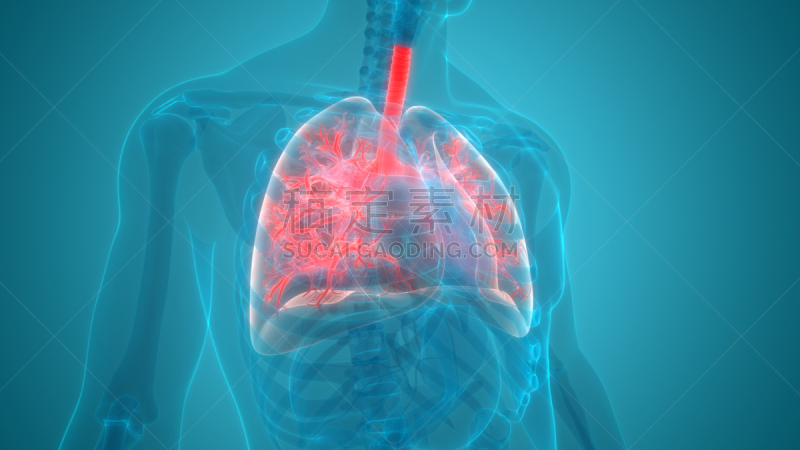

人体呼吸系统肺解剖学详情

JPG